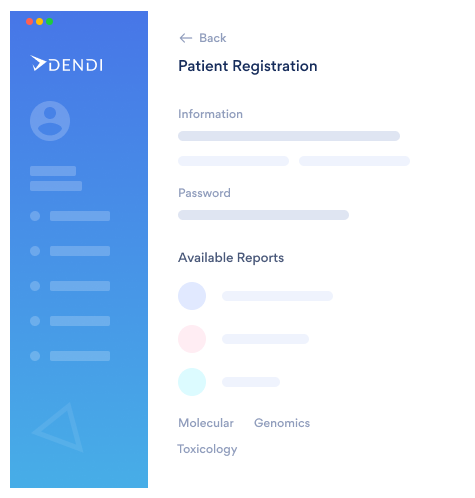

The only constant in healthcare is change. Dendi’s powerful

and user-optimized software platform equips clinical labs

with the tools needed to move forward with confidence.